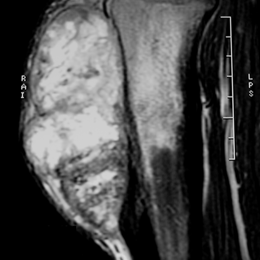

MRI of Periosteal Ostesarcoma